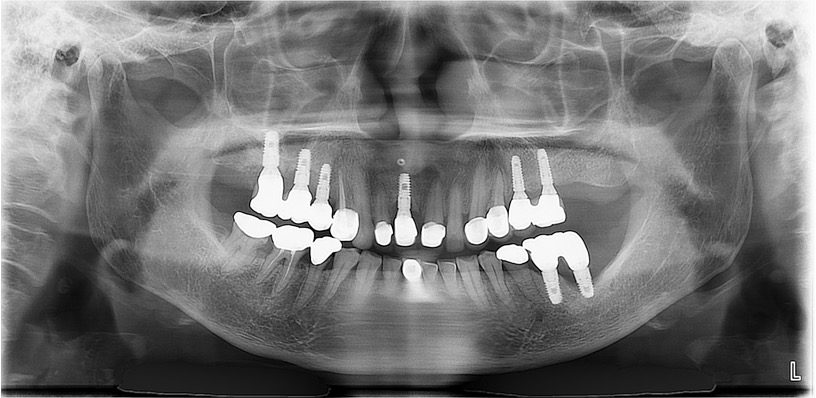

The patient developed persistent pain following osseointegration and prosthetic restoration. A panoramic radiograph revealed no significant lesions except for bone loss on the mesial side of implant #37 (Fig. 1). Despite multiple flap surgeries, the symptoms persisted. On November 26, 2015, implant #37 was removed in the Department of Periodontology at our hospital (Fig. 2A). As discomfort continued, she was referred to the Department of Oral and Maxillofacial Surgery on December 3, 2015, for further evaluation and management. Conservative treatment was attempted for 3 months; however, the lesion progressed, necessitating the extraction of implants #36 and #35 on March 4, 2016 (Fig. 2B and 2C). Six months later, sequestrum formation was observed (Fig. 2D). A sequestrectomy was subsequently performed, resulting in satisfactory healing of the left mandible (Fig. 2E and 2F). The patient discontinued Fosamax and was transitioned to Prolia (denosumab 60 mg, subcutaneous injection every 6 months) on June 2, 2021. Since then, she has continued to receive regular Prolia injections.

A 72-year-old woman was referred from the Department of Otorhinolaryngology for evaluation and removal of an implant on the right side of the mandible. She reported pricking pain in the right lower lip and mandibular region. Wide excision was planned due to oral mucosal dysplasia involving the lower right molar and tongue areas. Dental history revealed that implants had been placed in #44, #45, and #46 regions 4 years ago. The prosthesis was removed 2 years before because of persistent pain and discomfort. The patient had a history of Bonviva (ibandronate 150 mg with cholecalciferol 24,000 IU, orally once monthly) administration for osteoporosis, taken from 3 years before to 1 month before admission. She had also been treated for spinal stenosis and rheumatoid arthritis with methotrexate and systemic corticosteroids.